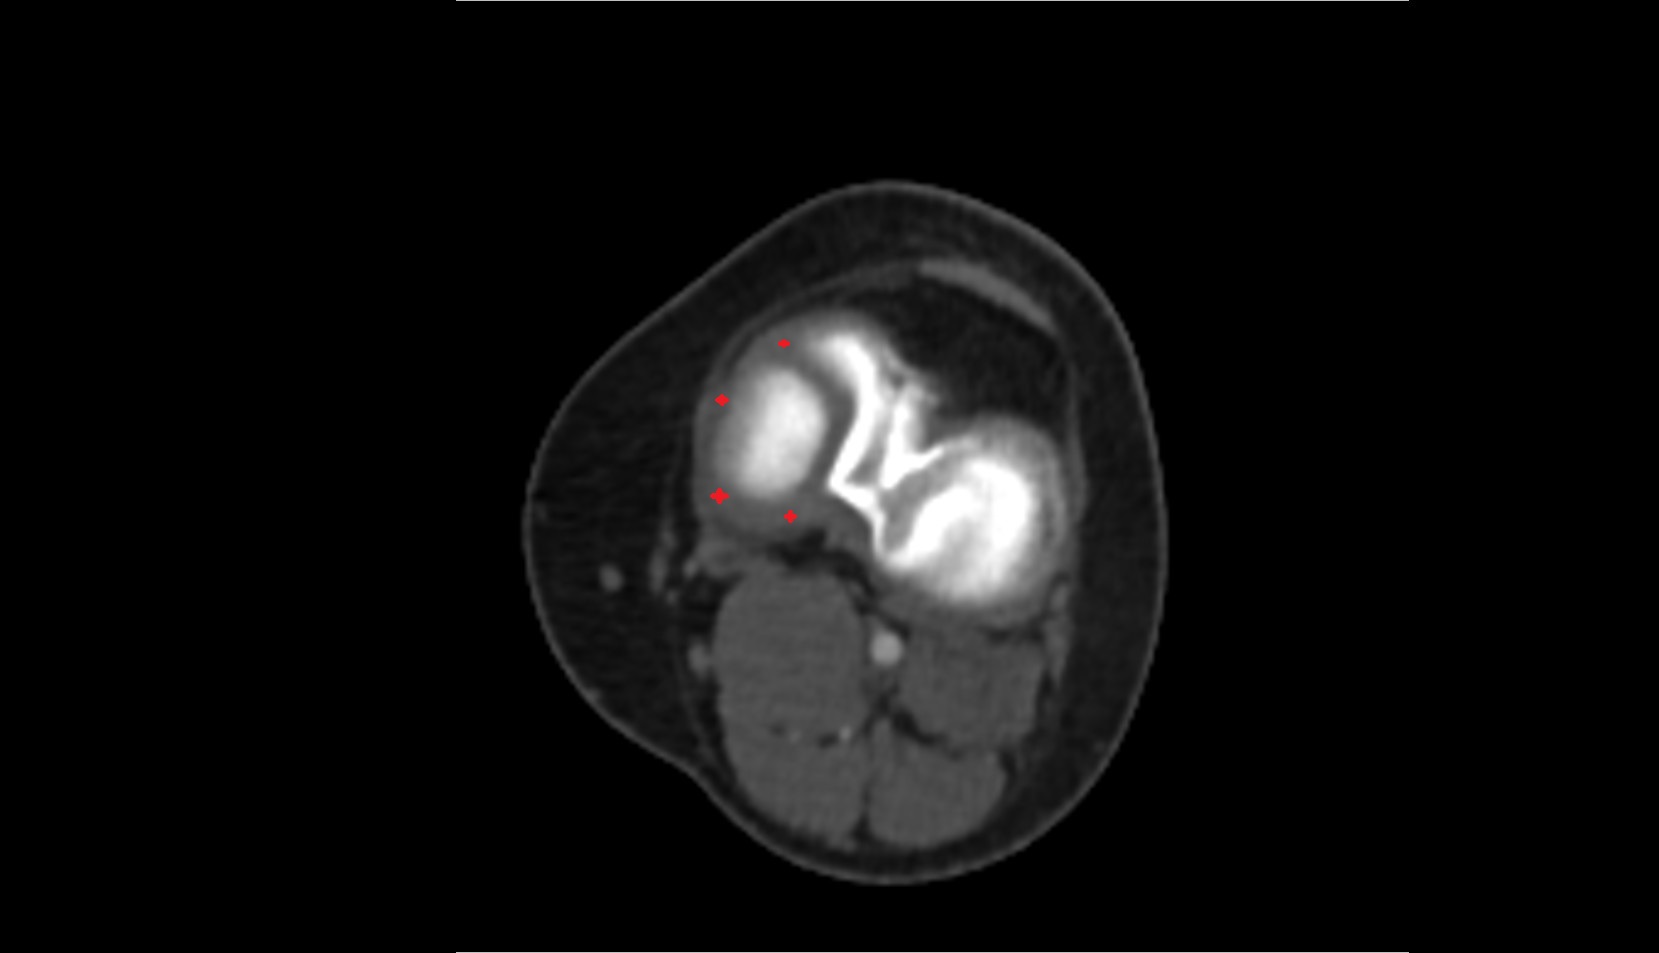

- Meniscus cartilage

- Medial meniscus

- Lateral meniscus

- Knee Joint